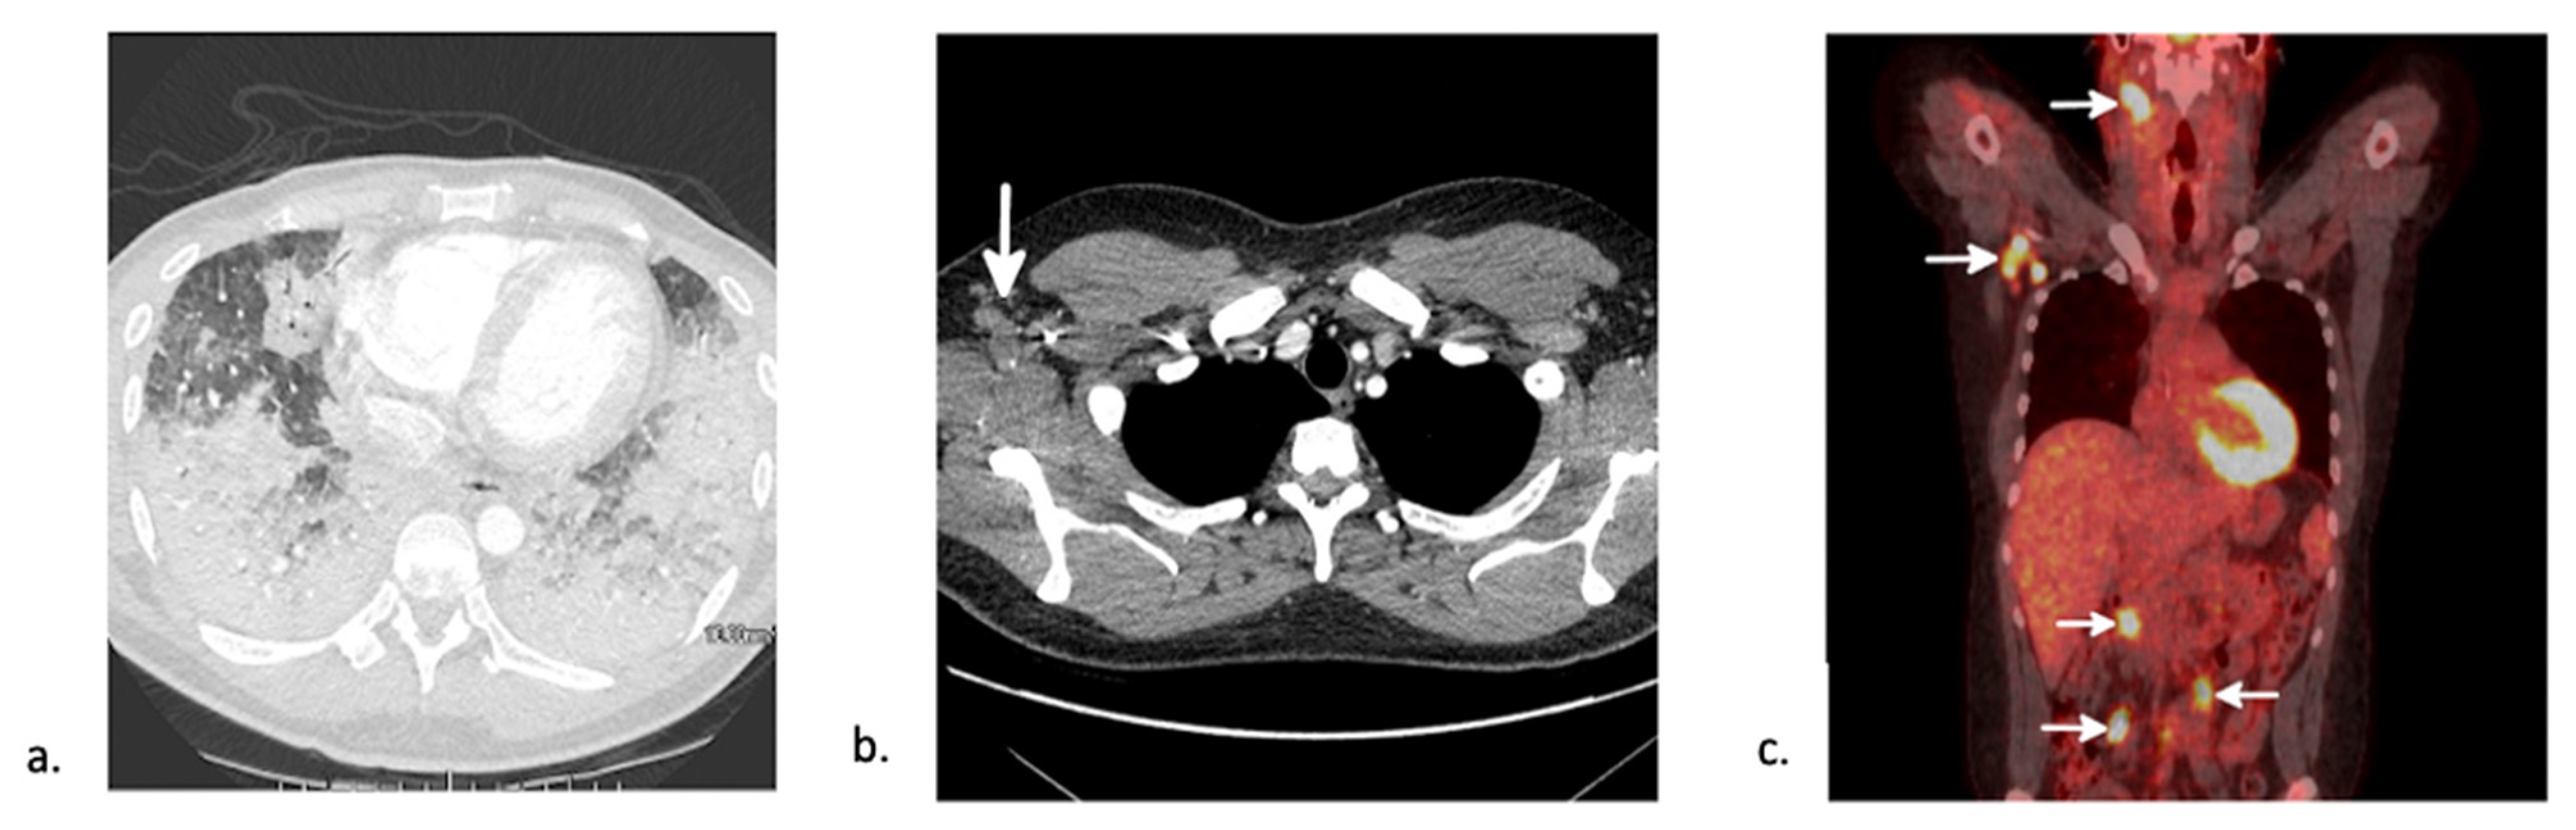

5.3. Post-Transplant Lymphoproliferative Disease (PTLD)

7.3. Viral Pneumonia